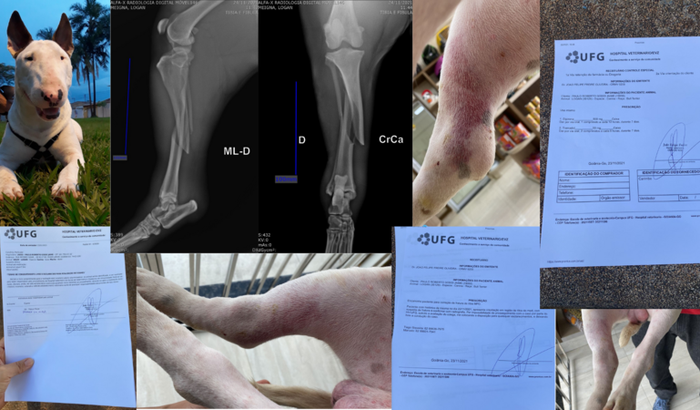

O Logan é um Bull Terrier que fará 1 ano no dia 07.12.2021.

O Logan é um cachorro dócil e sociável com pessoas e outros animais. Porém, um cachorro SRD do mesmo convívio, estava se alimentando e o Logan estava passando próximo, quando o outro cachorro avançou e eles iniciaram uma briga. Ao apartar, ele acabou batendo sua pata direta traseira na quinta de um tanque, aonde ocasionou em fratura da tíbia e fíbula MPD. O outro cachorro teve apenas ferimentos leves (arranhões), mas o Logan acabou se fraturando.

Após as consultas veterinárias e raio-X, O médico veterinário confirmou a fratura.Precisamos do valor para custear os exames de e todos os aparatos para realizar a cirurgia.